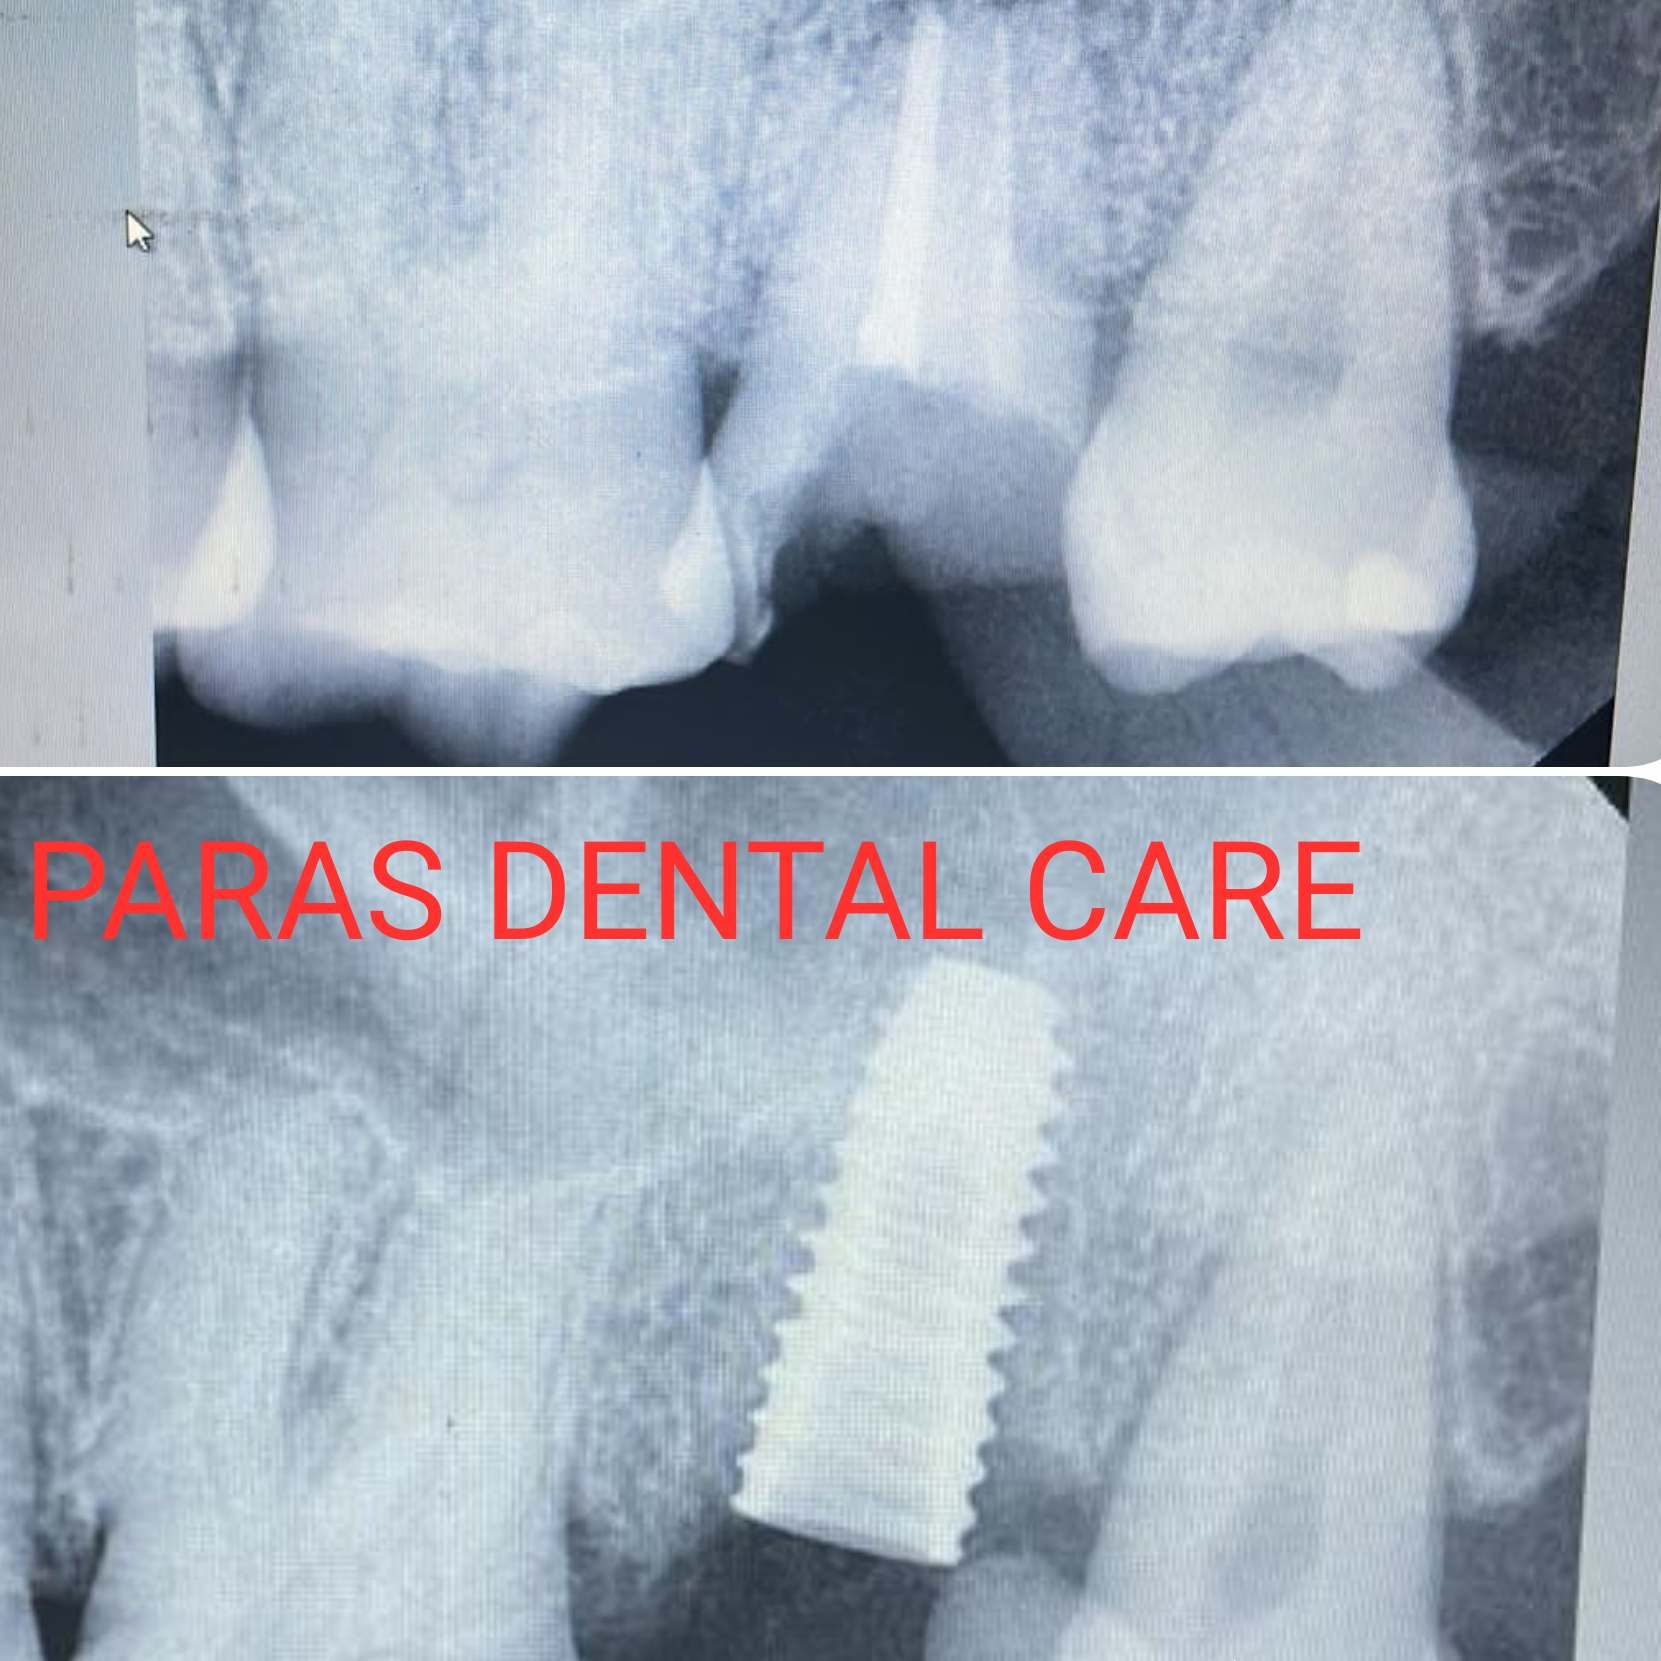

Patient came with a complaint of pain in upper back tooth. After clinical examination and radiograph assessment, our Implantologist did painless extraction of fractured tooth and immediately placed dental implant.